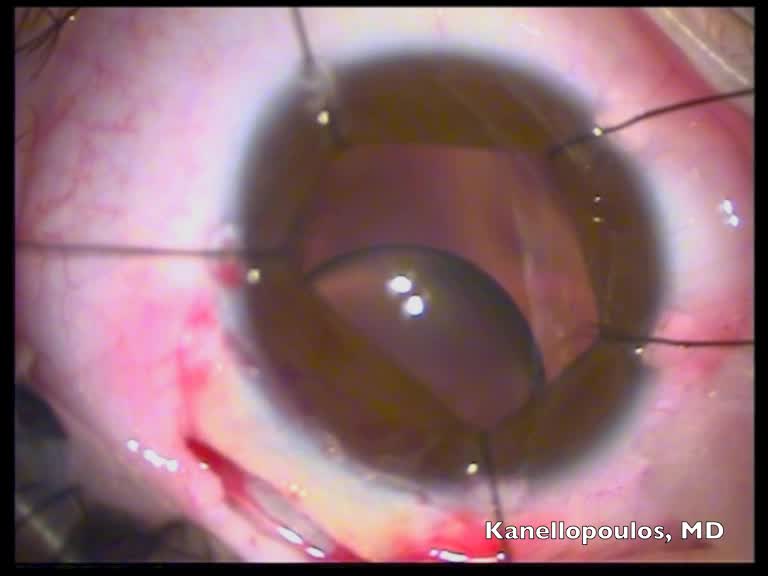

Ahmed Glaucoma Valve (AGV, New World Medical) implantation is an effective treatment for refractory pediatric glaucoma. Studies report success rates as high as 85-90% after 3-4 years, with success often defined as IOP within a specific range (5-21 mmHg) with or without medication. The AGV is attached to a small plate placed under the conjunctiva and is designed with a one-way flow restriction system to prevent hypotony.